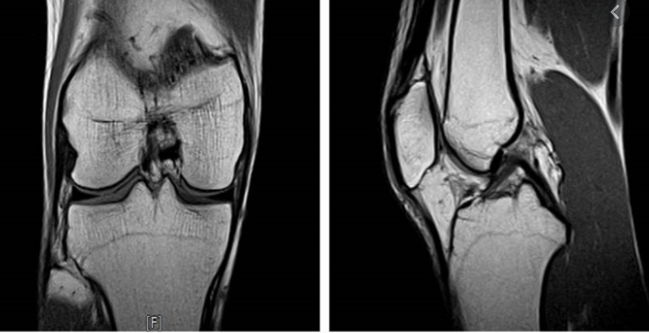

하지만 재정악화 및 무분별한 MRI 시행으로 또 제도가 바꼈습니다. 2020년 4월 1일에 개선안이 나왔는데요.

신경학적 검사상 이상 증상 또는 뇌혈관 질환이 강력하게 의심되는 경우에만 건강보험이 적용되는걸로 바꼈습니다.

그리고 뇌질환이 의심되는 두통, 어지로움으로 MRI 검사를 받았다면 본임부담이 80%로 바꼇습니다. 그렇기 때문에 의사의 판단하에 따라 금액이 많이 차이가 나게 되었습니다.

보통 MRI 보험적용은 의사의 진료하에 따라 확인이 가능하게됩니다. 이상소견이 없다면 비급여로 처리되기 때문에 금액이 최소 50~100만원 정도 금액이 청구됩니다.